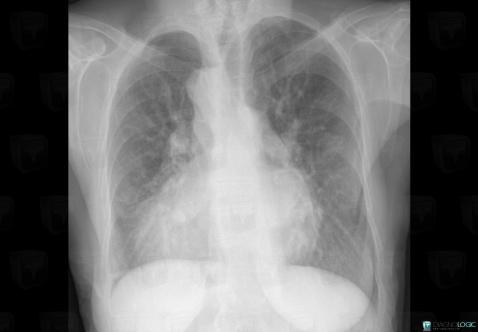

The images below illustrate this case for diagnoses Situs inversus, for the modalities (X rays)

Situs inversus, Cardiac cavities / Pericardium, X rays

- Diagnosis Situs inversus, Location(s) Cardiac cavities / Pericardium, with gamuts